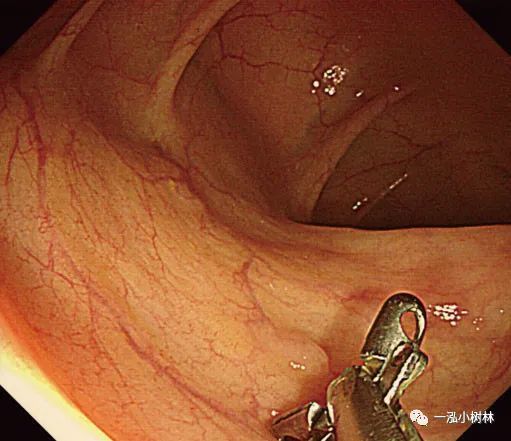

2.最近的一项随机研究表明,在内镜下对小息肉的治疗中,CSP技术优于冷钳息肉切除术,并且在完整性和操作时间方面均优于冷钳息肉切除术。

3.将息肉边缘正常黏膜包括在内,用圈套器夹住并机械横切。切取的速度要快,因为慢的横切会造成黏膜下组织大量的损伤和随后不必要的出血。

4.下一个重要步骤是将息肉切除部位的标本通过结肠镜钳道吸入。切除息肉后,应将结肠镜头指向切除部位,随后吸引。